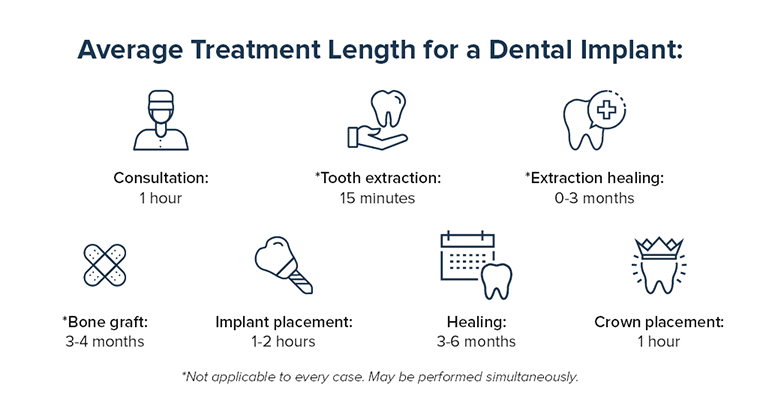

How:long does it take for dental implants from initiation to end treatment?

How long does it take to fix dental implants? Dental implants take an average of six to eight months to complete the daily routine without help with healing.

What are the 3 stages of dental implants?

Three Phases of Dental Implant Surgery

- Implant location.

- Attaching the stirrup.

- Adapting the crown.

What is the first stage of a dental implant?

The first phase of the dental implant process is the burial of the implant in the jaw bone through a surgical procedure. The dental implant replaces the root of the tooth and needs time to heal. During this healing time, osseointegration (integration of the bone with the implant itself) occurs.